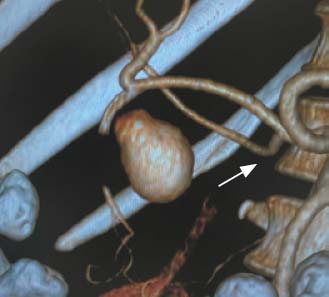

Эффективность рентгенэндоваскулярного лечения, заключающаяся в остановке продолжающегося желудочно-кишечного кровотечения и профилактике его рецидивов, составила 100%. Эффективность имплантации стентов-графтов подтверждена с помощью контрольной ангиографии. На рис. 2 и 3 представлены фотографии ангиограмм брюшного отдела аорты и ангиографические результаты имплантации стента-графта в желудочно-двенадцатиперстную артерию в области шейки ложной аневризмы.

Рис. 3. Ангиограмма желудочно-двенадцатиперстной артерии. Стрелкой указан стент-графт, имплантированный в желудочно-двенадцатиперстную артерию, ложная аневризма не контрастируется, ветви собственной печёночной артерии проходимы